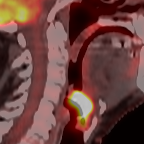

This paper presents an overview of the second edition of the HEad and neCK TumOR (HECKTOR) challenge, organized as a satellite event of the 24th International Conference on Medical Image Computing and Computer Assisted Intervention (MICCAI) 2021. The challenge is composed of three tasks related to the automatic analysis of PET/CT images for patients with Head and Neck cancer (H&N), focusing on the oropharynx region. Task 1 is the automatic segmentation of H&N primary Gross Tumor Volume (GTVt) in FDG-PET/CT images. Task 2 is the automatic prediction of Progression Free Survival (PFS) from the same FDG-PET/CT. Finally, Task 3 is the same as Task 2 with ground truth GTVt annotations provided to the participants. The data were collected from six centers for a total of 325 images, split into 224 training and 101 testing cases. The interest in the challenge was highlighted by the important participation with 103 registered teams and 448 result submissions. The best methods obtained a Dice Similarity Coefficient (DSC) of 0.7591 in the first task, and a Concordance index (C-index) of 0.7196 and 0.6978 in Tasks 2 and 3, respectively. In all tasks, simplicity of the approach was found to be key to ensure generalization performance. The comparison of the PFS prediction performance in Tasks 2 and 3 suggests that providing the GTVt contour was not crucial to achieve best results, which indicates that fully automatic methods can be used. This potentially obviates the need for GTVt contouring, opening avenues for reproducible and large scale radiomics studies including thousands potential subjects.